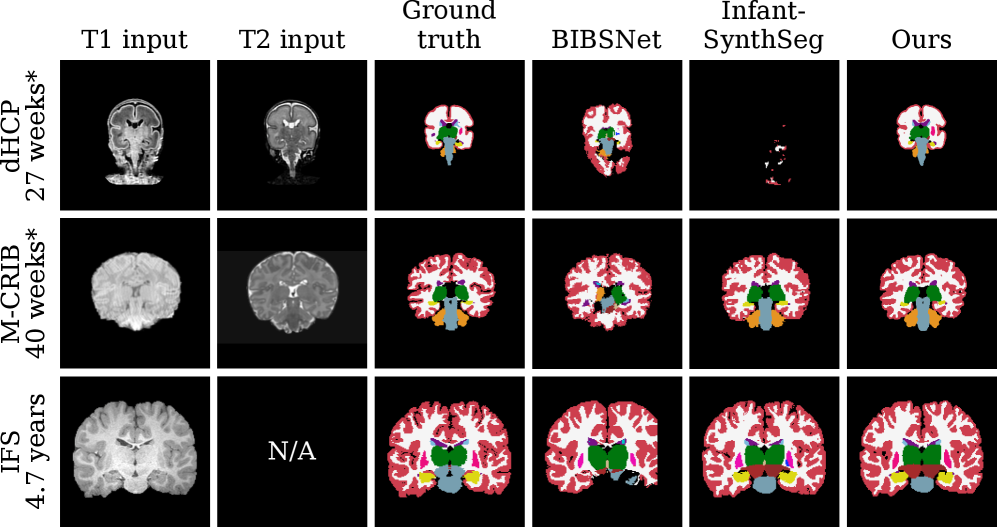

Fig. 8 visualizes sample segmentations for each method, evaluated using all available input contrasts. Qualitatively, BabySeg generalizes to severely preterm neonates scanned at 26 weeks postmenstrual age, while the baseline methods substantially over- or undersegment. BabySeg and Infant-SynthSeg accurately segment the oldest IFS subject scanned at 4.7 years. In contrast, BIBSNet’s prediction undersegments, likely because the size of the brain exceeds the FOV covered by the template it uses for internal registration.

Refer to caption

Figure 8: Segmentation examples across methods. Each row shows a subject from a different test set. Asterisks represent postmenstrual age.